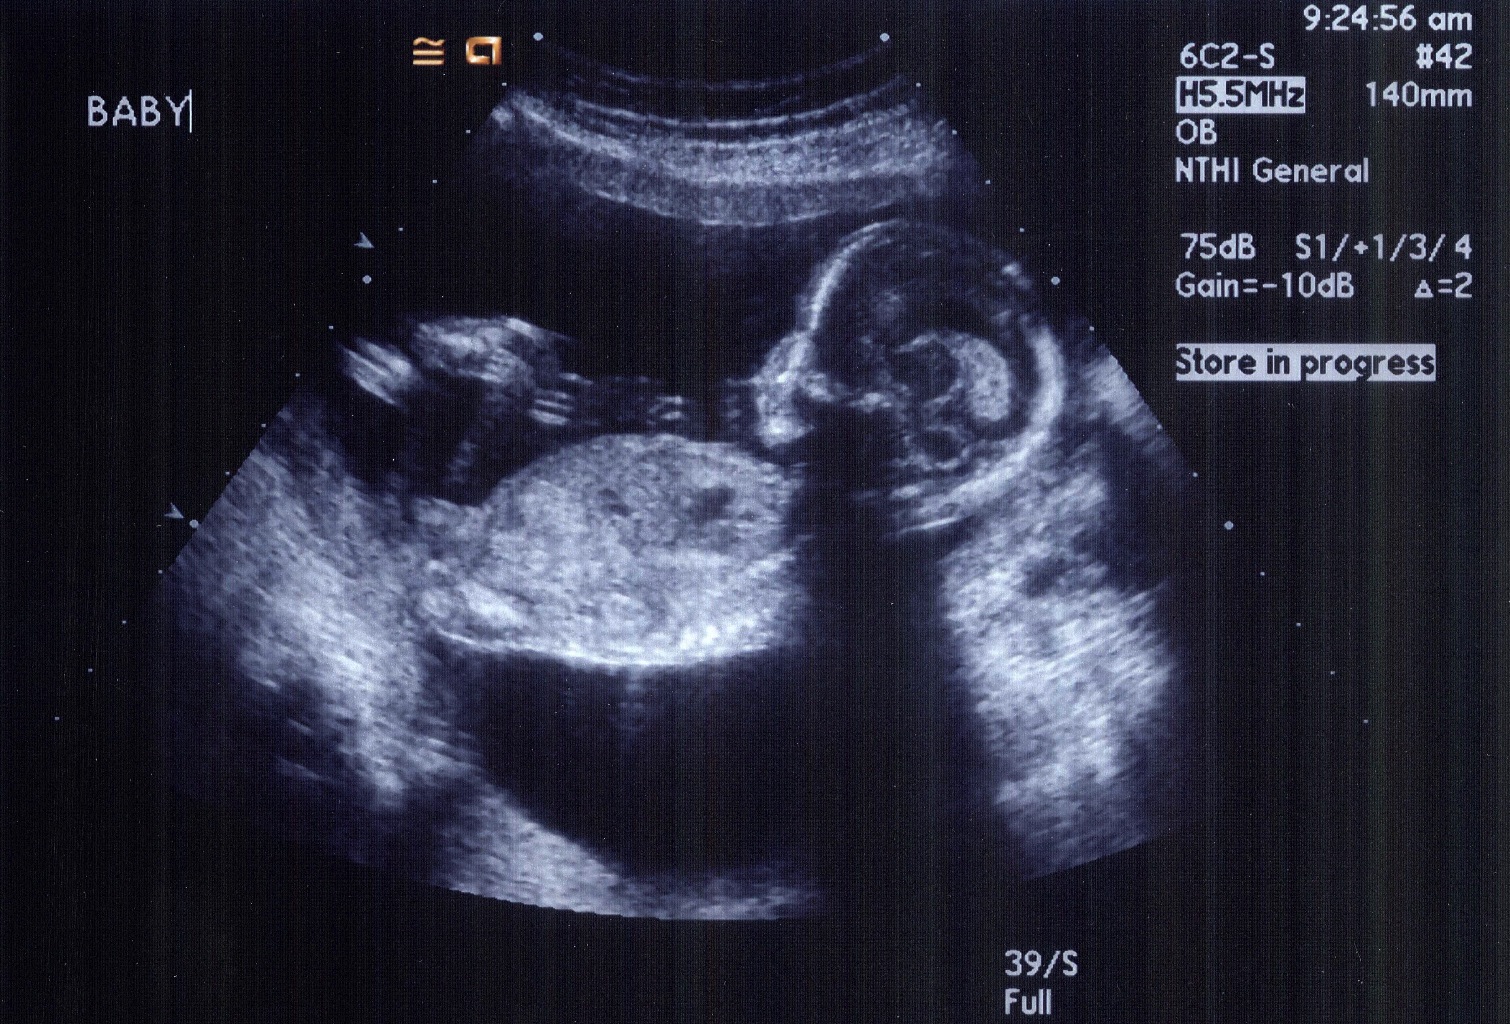

It's a Girl!